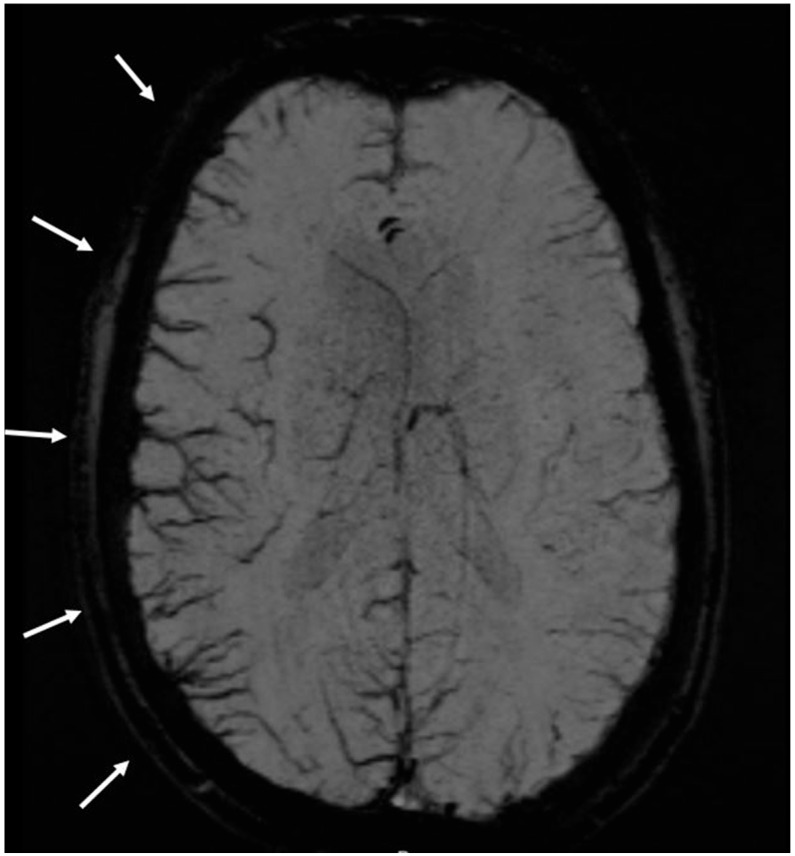

Background: The asymmetry of cortical veins in susceptibility weighted imaging (SWI) in MRI might be a biomarker for migraine auras and cortical spreading depression (CSD). The aim of this study was to assess in humans if SWI asymmetry can be found in patients who have migraine attacks without auras.

Results: In the migraines with auras group, SWI asymmetry was found in 26% (95% CI 18-35) compared to patients with migraines without auras (3%, [95% CI 1-8], p < 0.001) and controls 7% [95% CI 3-14], p < 0.001). There was no difference between patients with migraines without auras and controls (p = 0.19).

Conclusions: The distinct SWI changes in migraines with and without auras suggest that CSD might not be involved in the pathophysiology of migraines without auras.